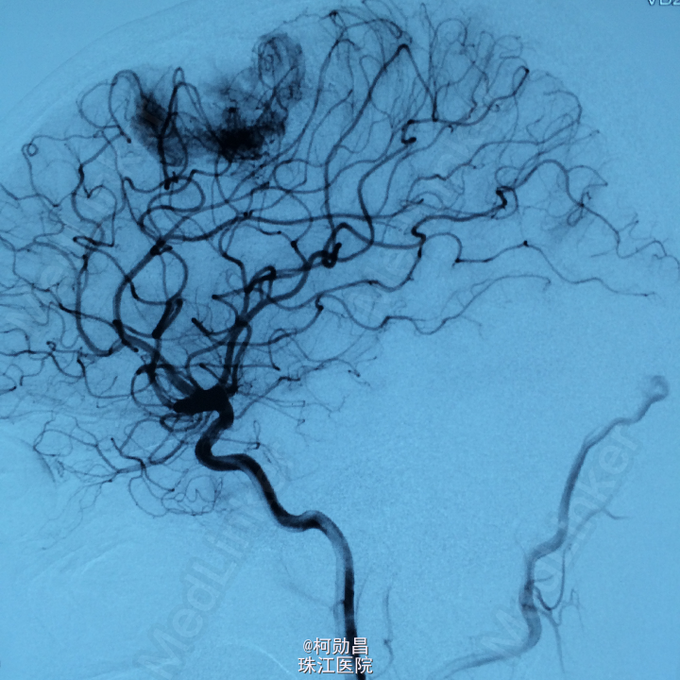

主诉:头痛伴右上肢麻木无力两个月,加重七天 病史:两个月前出现头痛,走路不稳,右上肢无力,不能持物,过去两个月曾有两次癫痫全面发作,发作时意识丧失,但无尿失禁及舌头咬伤。查头MRI示右侧顶叶占位,考虑脑膜瘤。

查体:巴氏征阳性,左侧肢体感觉减退,肌力正常,余无特殊阳性。 辅助检查:查头MRI示右侧顶叶占位,考虑脑膜瘤。

诊断:左侧顶叶占位 处理:行DSA检查,提示肿瘤染色,予PVA颗粒行血管内栓塞治疗。

术后再予开颅手术治疗,书中见供血动脉闭塞,出血量少。